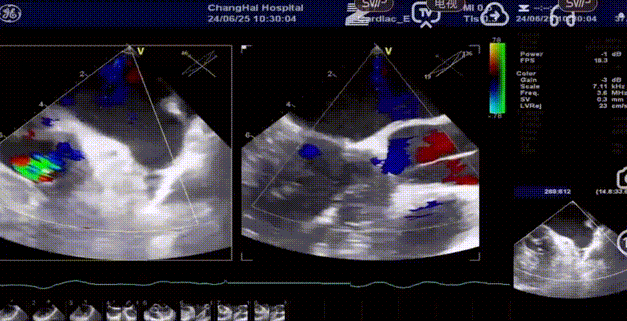

术前超声

术后超声

手术过程顺利,器械操作用时仅10分钟。术中通过造影确认右冠窦居中,定位件准确入窦,瓣膜释放顺利。经超声评估,无瓣周漏,手术过程衔接流畅,未出现其他特殊情况。

术后患者恢复良好,心功能显著改善。影像复查显示瓣膜功能正常,无反流及瓣周漏,未见心律失常、出血等并发症。平均主动脉跨瓣压差5mmHg,整体状态稳定,心功能与生活质量均有明显提升。